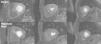

A and C: T2-weighted turbo spin-echo sequences, 2-chamber (A) and short-axis (C) views, showing T2 hyperintense signal at the transition between the mid and apical inferior segments; B and D: same views in T1-weighted double inversion recovery sequences, showing subepicardial delayed enhancement at the same point.

A 51-year-old man, hypercholesterolemic and an ex-smoker, was hospitalized for sudden-onset typical chest pain. The admission electrocardiogram showed slight ST-segment elevation with downward concavity in II, III and aVF (Figura 1). Urgent coronary angiography revealed a large caliber anterior descending artery, with a short proximal lesion and a long lesion in the mid segment, both with around 50% stenosis (Figura 2); there were no significant lesions in the left main, circumflex or right coronary arteries. Laboratory tests showed elevated biomarkers of myocardial necrosis (troponin 11.8μg/l, reference value <0.04μg/l). The echocardiogram showed good global and segmental left ventricular function. Stress cardiac magnetic resonance imaging (MRI) was requested, with a view to aiding differential diagnosis between myocardial infarction with spontaneous reperfusion and myopericarditis, as well as to assess the ischemic repercussions of the lesions in the anterior descending artery. This was performed on the sixth day of hospital stay, and showed focal subepicardial delayed enhancement at the transition between the mid and apical inferior segments, with a slightly increased T2 signal suggestive of edema at this point (Figura 3), and normal perfusion during the first pass of paramagnetic contrast under adenosine stress and at rest (Figura 4). A diagnosis of myocarditis was therefore made, given the absence of stress-induced ischemia. The lack of subendocardial delayed enhancement meant that infarction with spontaneous reperfusion could be definitively excluded. The patient was discharged one week after the acute event and has since remained asymptomatic.